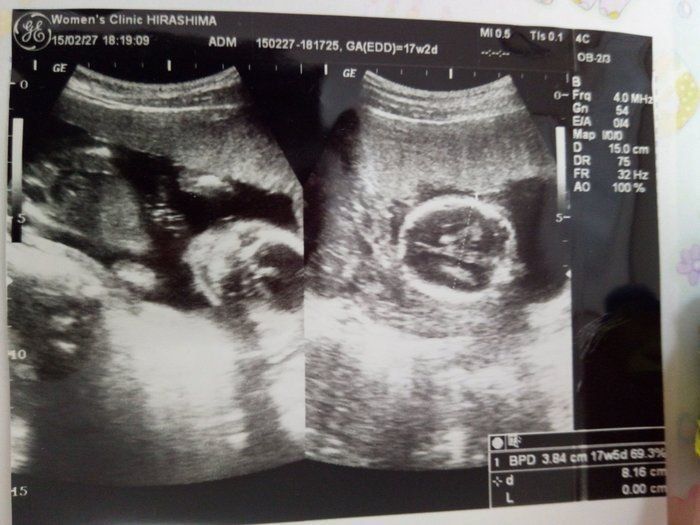

17週 性別 女の子 エコー-妊娠17週0日(17w0d)の超音波(エコー)写真 (*´艸`) 性別分かるかなぁーと思ったけど足をクロスしてて、分からず CRL1086cmBPD38cm 多分女のこかなぁ~と、思ってますが(^o^) (5円玉 回ったし、中国式カレンダーも女の子でした) 一人目が女の子なので 姉妹になるといいけど元気に健康で産 妊娠16週5日(16w5d)で性別がわかった! 妊娠16週5日(16w5d)のエコー画像 妊娠16週で性別が男の子と確定したエコー画像 PR出産準備が10%オフ!Amazonベビーレジストリに登録しよう! 流産リスクなしの出生前検診って知ってる?

Amiさんの妊娠17週目のエコー写真 推定体重は3773g! 骨盤に入らず緊急帝王切開になった長女の成長をエコー写真で振り返る 右側のエコー写真には、お尻と脚が2本写っています。 このエコー検査から「性別は女の子かもしれない」と主治医の先生から言わ 妊娠18週|赤ちゃんの胎動や性別エコーの様子は?体重増加に注意 妊娠5ヶ月|体重増加や胎動、ママのお腹や胎児の大きさは? 出典:wwwamazoncojp みんなの妊娠18週目のエコー写真をご紹介します。 18週0日(18w0d・女の子)|surfrie さん(38歳) エコー写真撮影時のエピソード: なぜか、毎回17週 エコー 性別 Dr林「性別は必ず判定できるとは限らない」 最近では妊婦さんほぼ全員が、性別判定を希望します。 ただし、教えない方針の病院もあり、全部の医療機関が性別を教えるわけではありません。 また、技術的には男の子は妊娠14~15週、女の子は妊娠17~18週には判断できます